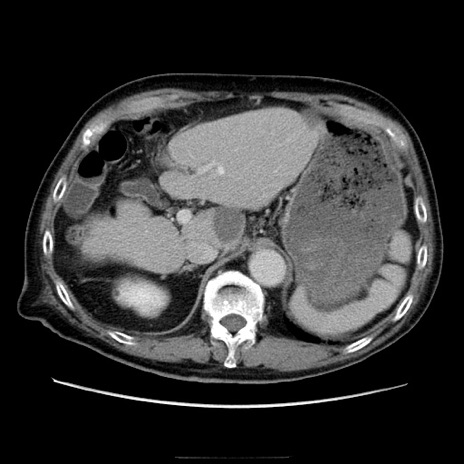

症例21(横断像)

【症例】70歳代男性

【主訴】腹痛

【現病歴】肝硬変・肝細胞癌にてかかりつけの方。約9時間前に食後より腹痛出現。症状が徐々に増悪し、嘔吐出現したため来院。

【既往歴】肝硬変、肝細胞癌(RFA、TACE後)

【身体所見】意識清明、表情苦悶様、BT 36℃、BP 129/78mmHg、P 88bpm、SpO2 97%(RA)、右上腹部から心窩部にかけて圧痛あり、反跳痛なし、筋性防御あり。

【データ】WBC 5800、CRP 0.16